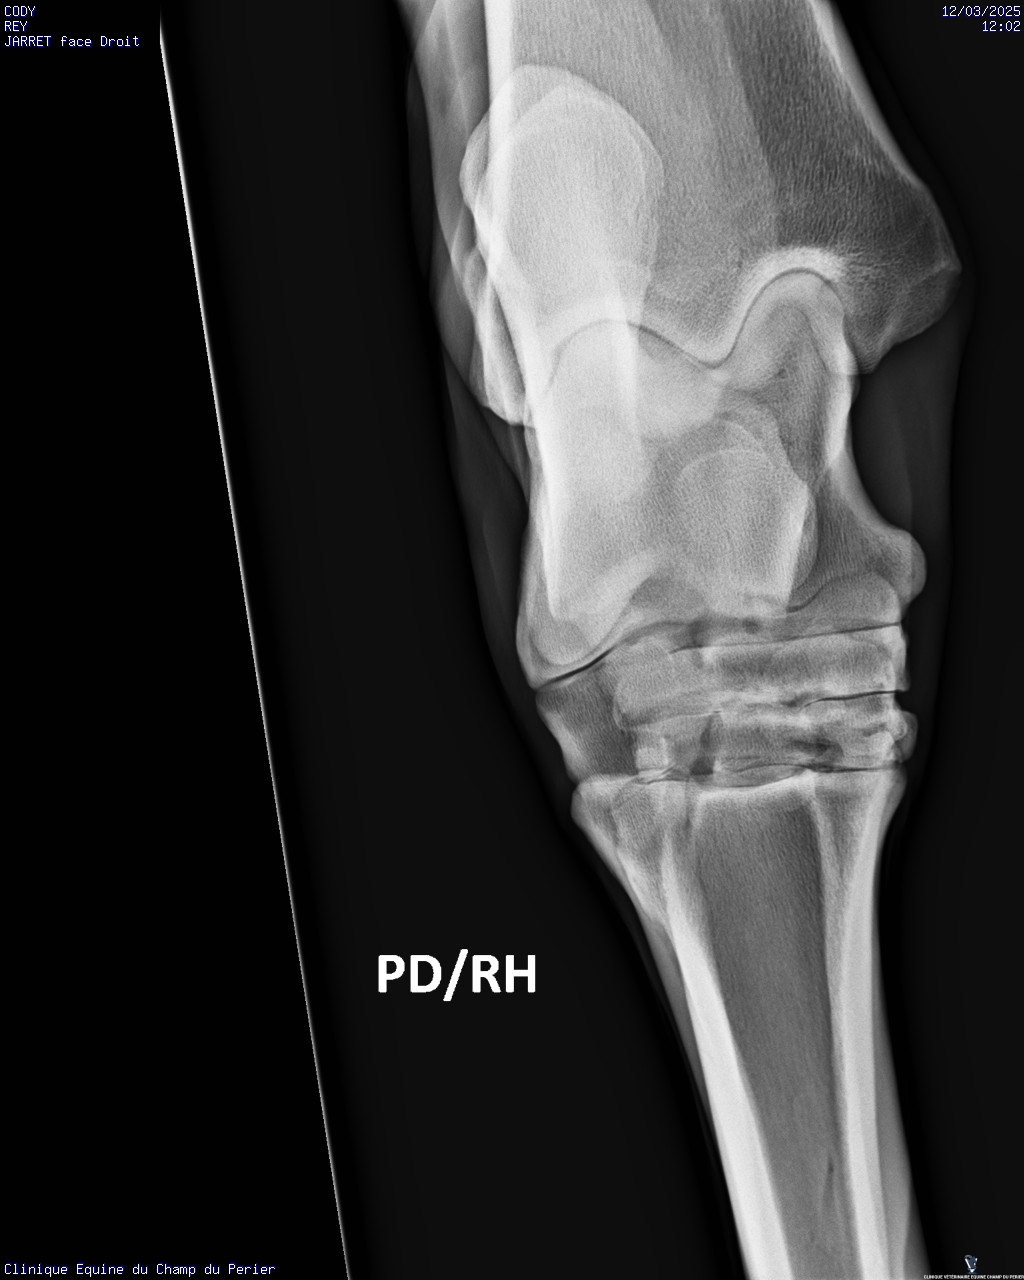

| Dire merci | Voici les résultats : - pieds antérieurs : novembre 2024 : perte de parallélisme entre les 3° phalanges des deux antérieurs et les sabots-parois dorsales ; pieds trop longs en pinces - pieds postérieurs ce jour : très léger défaut de parallélisme entre P3 et parois dorsales des sabots, mais pinces trop longues. Un défaut en phase de correction sou le sabot PG, en ponte de fourchette. On note aussi un ostéophyte au sommet dorsal de P2 sur le PD. - jarrets : on note sclérose des os centraux et troisièmes os des tarses + lyse forte de ces deux os sur le jarret gauche Ccl : comme indiqué sur mon ordonnance il faut : - parer les sabots afin d’obtenir au fur et à mesure le parallélisme entre les 3° phalange et les parois dorsales des sabots ; parer les pinces des sabots au plus court - poser des fers qui seront bien reculés et donneront de la surface d’appui en talons, sur les deux antérieurs - soulager la douleur pour les deux mois à venir avec Equioxx° un comprimé par jour. Le contrôle des enzymes rénales – normales – fait se jour le permet. - traiter CODY avec des biphosphonates (Osphos°, voire Tildren°) |

| Dire merci | C'est quoi une forte lyse ? C'est ça qui lui avait fait gonflé le jarret ? Finalement pas de fourbure ? (Tant mieux) (Et pour les anomalies que tu avais entouré en bleu sur les anciennes radio ? Il a dit quelque chose de spécial ?) |

| Dire merci | C'est pas une perte d os un peu comme l'osteoporose? Et donc un.machin lié à arthrose? Un veto pour expliquer? Message édité le 12/03/25 à 21:18 |

| Dire merci | Oui l’ostéolyse c’est la destruction du tissu osseux. Mais il n’avait jamais eu de radios du jarret G dans les multiples examens déjà faits? Parce que c’est vraiment pas beau là ![]() |

| Dire merci | Mais il n’avait jamais eu de radios du jarret G dans les multiples examens déjà faits? Parce que c’est vraiment pas beau là Je suis d'accord avec toi Juliie . Je ne voulais pas intervenir directement après le post des radios pour ne pas être la rabat-joie. Mais c'est pas job job au niveau des articulations (toutes les articulations en fait). Enfin le véto a dû te le dire. Quand ils préconisent du Tildren c'est que c'est déjà sérieux et bien avancé (en gros, le Tildren essaye de "bloquer" l'articulation en l'état pour ne pas que ça se dégrade davantage et je crois qu'il a aussi une action antalgique). Il a quel âge ton cheval ? Message édité le 12/03/25 à 23:45 Message édité le 12/03/25 à 23:45 |

| Dire merci | L'état du jarret gauche n'est pas bon. Il n'y a jamais eu de radios de faites, les différents pros m'ont dit que c'était sa conformation. J'ai dû insister pour faire les radios. Avec mon véto habituel on va programmer un tildren assez rapidement. Cody va prendre 11 ans cette année. De ce que j'ai compris les antérieurs douloureux font qu'il y a un report du poids sur les postérieurs. La priorité est de soulager la sensibilité des antérieurs, pas de chance le maréchal-ferrant s'est trompé de taille de fers, le ferrage est reporté de 10 jours. En attendant je dois donner un cachet d'equiox par jour. |